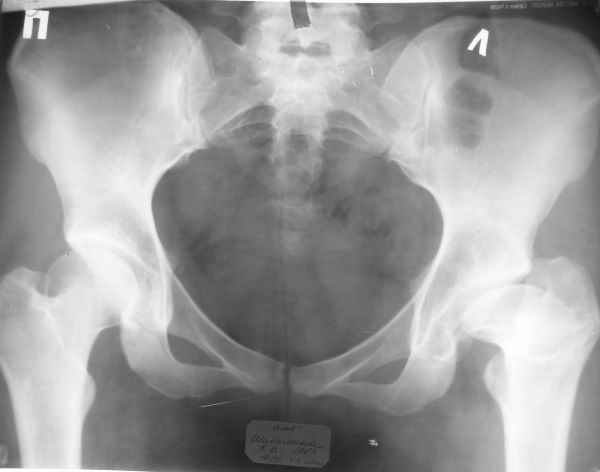

Пациентка 23 лет, доставлена в клинику с Диагнозом: Закрытый сегментарный оскольчатый перелом левой бедренной кости в верхней и средней трети. Травма в результате ДТП 10.03.2006г. Из анамнеза у пациентки диспластический левосторонний коксартроз, S-образный сколиоз 2ст. В 1999г в Кургане выполнялась остеотомия бедра в нижней трети и коррекция укорочения конечности на 3 см (рентгенограммы бедра и таза до травмы в приложении). До получения травмы пациентка ходила без боли с полной нагрузкой на левую ногу. Учитывая дисплазию левого ТБС, пациентке, вероятно, предстоит операция тотального эндопротезирования лев ТБС, что требует анатомичного восстановления проксимальногоотдела бедра. Рассматриваются следующие вариант остеосинтеза:1) Экстракортикальный остеосинтез проксимального и дистального перелома пластиной с угловой стабильностью типа LISS( г Рыбинск); 2) Ретроградный интрамедуллярный блокированный остеосинтез дистального перелома и накостный синтез проксимального пластиной с угловойстабильностью; 3) Остеосинтез бедра в аппарате внешней фиксации с фиксацией таза и возможной открытой адаптацией фрагментов. Хотелось бы узнать Ваше мнение. С уважением Украинский Евгений, г.Краснодар, ККБ N1, ТОО N3.

Судя по снимкам до перелома, большой вертел располагался высоковато. Может, подумать о том, чтобы при остеосинтезе его переместить дистальнее и/или латеральнее? Что скажут коллеги, активно занимающиеся эндопротезированием?